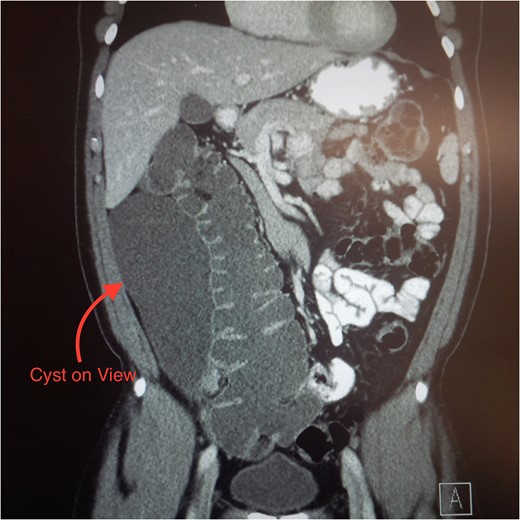

Mesothelial inclusion cyst is a rare benign tumour that has only 130 cases reported in the literature. Accurate diagnosis and optimal management of this condition remains uncertain. We report a 51-year-old African gentleman, whom presents with abdominal pain and constipation. A computed tomography scan was performed and revealed a large cystic lesion in the right paracolic gutter. The differential diagnosis included appendiceal mucinous neoplasm, cystic tuberculosis and duplication cyst. A laparotomy was performed due to his symptoms and size of the cyst. Macroscopically, the tumour had a size of 25 × 10 × 10 cm and revealed a necrotic lymph node. It was resected en bloc with the appendix and an ileocolic anastomosis performed. Histology revealed a diagnosis of mesothelial inclusion cyst and acute appendicitis. The patient recovered well and had no recurrence at 2-year follow-up.

Patients with mesothelial inclusion cysts usually present with a wide range of symptoms, including increasing abdominal girth, unspecific abdominal pain, nausea and vomiting [3]. Differential diagnoses to consider include: appendicitis, diverticulitis, Meckel's diverticulum, duplication cyst or cystic neoplasms [4]. CT scans and ultrasound visualize the lesion but do not differentiate from other intra-abdominal pathologies [5].